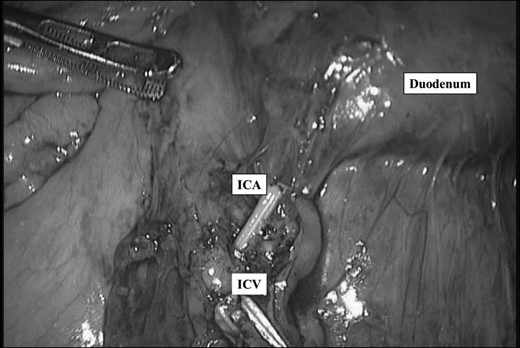

After ligation of ileocecal artery and vein. ICA: Ileocecal artery ICV: Ileocecal vein.